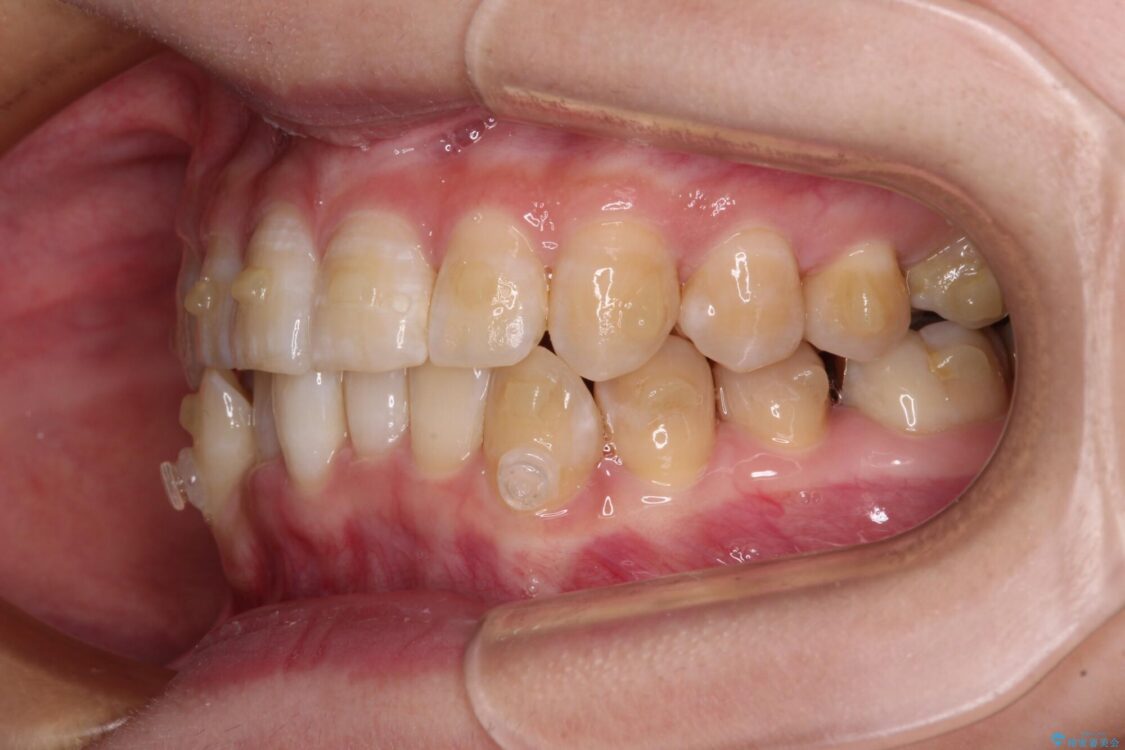

下顎の八重歯を気にして来院された患者様です。

下顎前歯にデコボコが集中していたため、顎間ゴムによる後方移動とIPR(歯と歯の間を削ること)により歯列を整えることとしました。

治療前、下顎前歯のデコボコが集中しており、奥歯の咬み合わせは、上顎に対して下顎が前方位にある状態でした。下顎の歯列を後方へ移動させる治療はインビザラインの得意とするところですので、1年程度で無事に治療を終えることができました。

治療前

• 【モニター】下顎前歯のデコボコをインビザラインできれいに 治療前画像